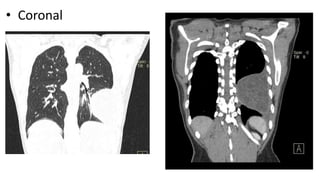

• Axial C+ arterial phase

Axial lung window

• Coronal